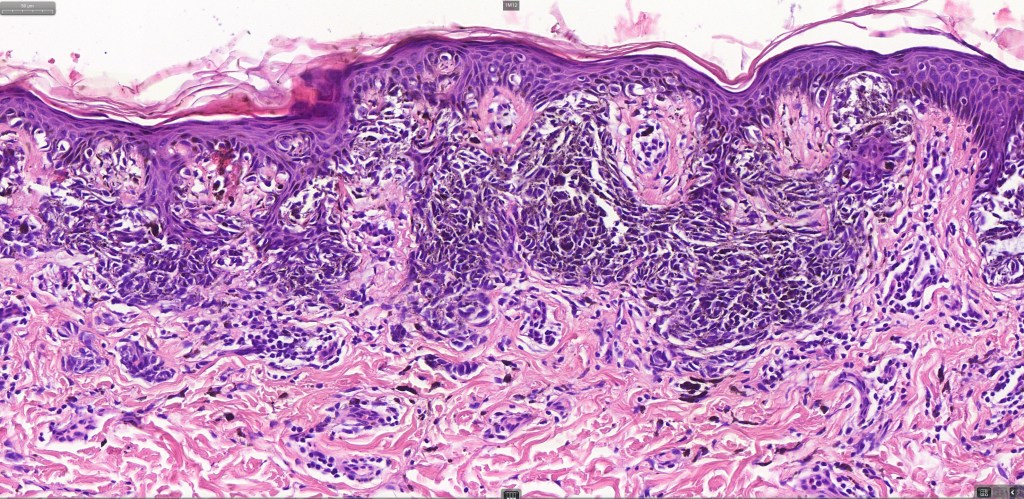

•Variant of Spitz nevus, readily identifiable at scanning magnification in the majority of cases

•Symmetrical and circumscribed with a characteristically flat lower border

•Vertically orientated oval junctional nests

. Heavy pigmentation although hypopigmented/amelanotic varinats can be encountered

•Acanthosis & hyperkeratosis

•Spindle cells with small nucleoli

•Mild pleomorphism

•Kamino bodies